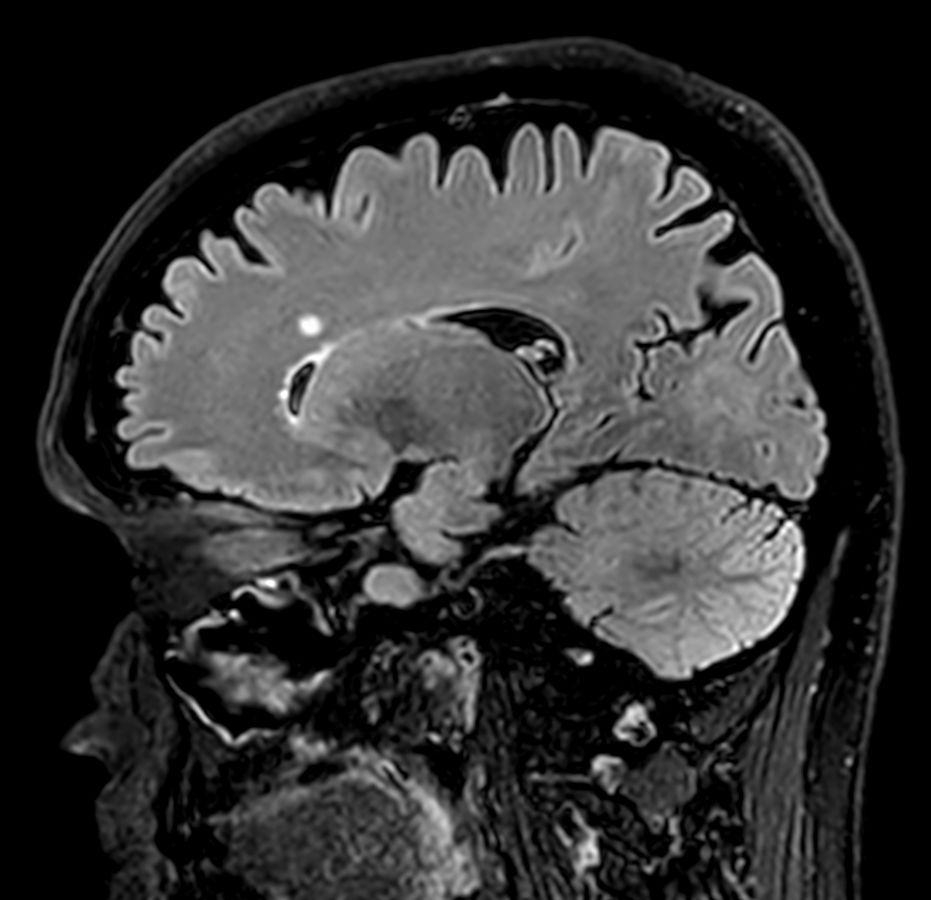

3D T2w FLAIR Compressed SENSE

3D T2w FLAIR (Reformat) Compressed SENSE